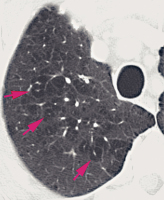

Computertomographie-COPD

Abbildung 4: Automatisierte Vermessung der größeren Atemwege durch eine dedizierte Software. Die einzelnen Atemwege werden mit Hilfe der Software semiautomatisch identifiziert und vermessen.